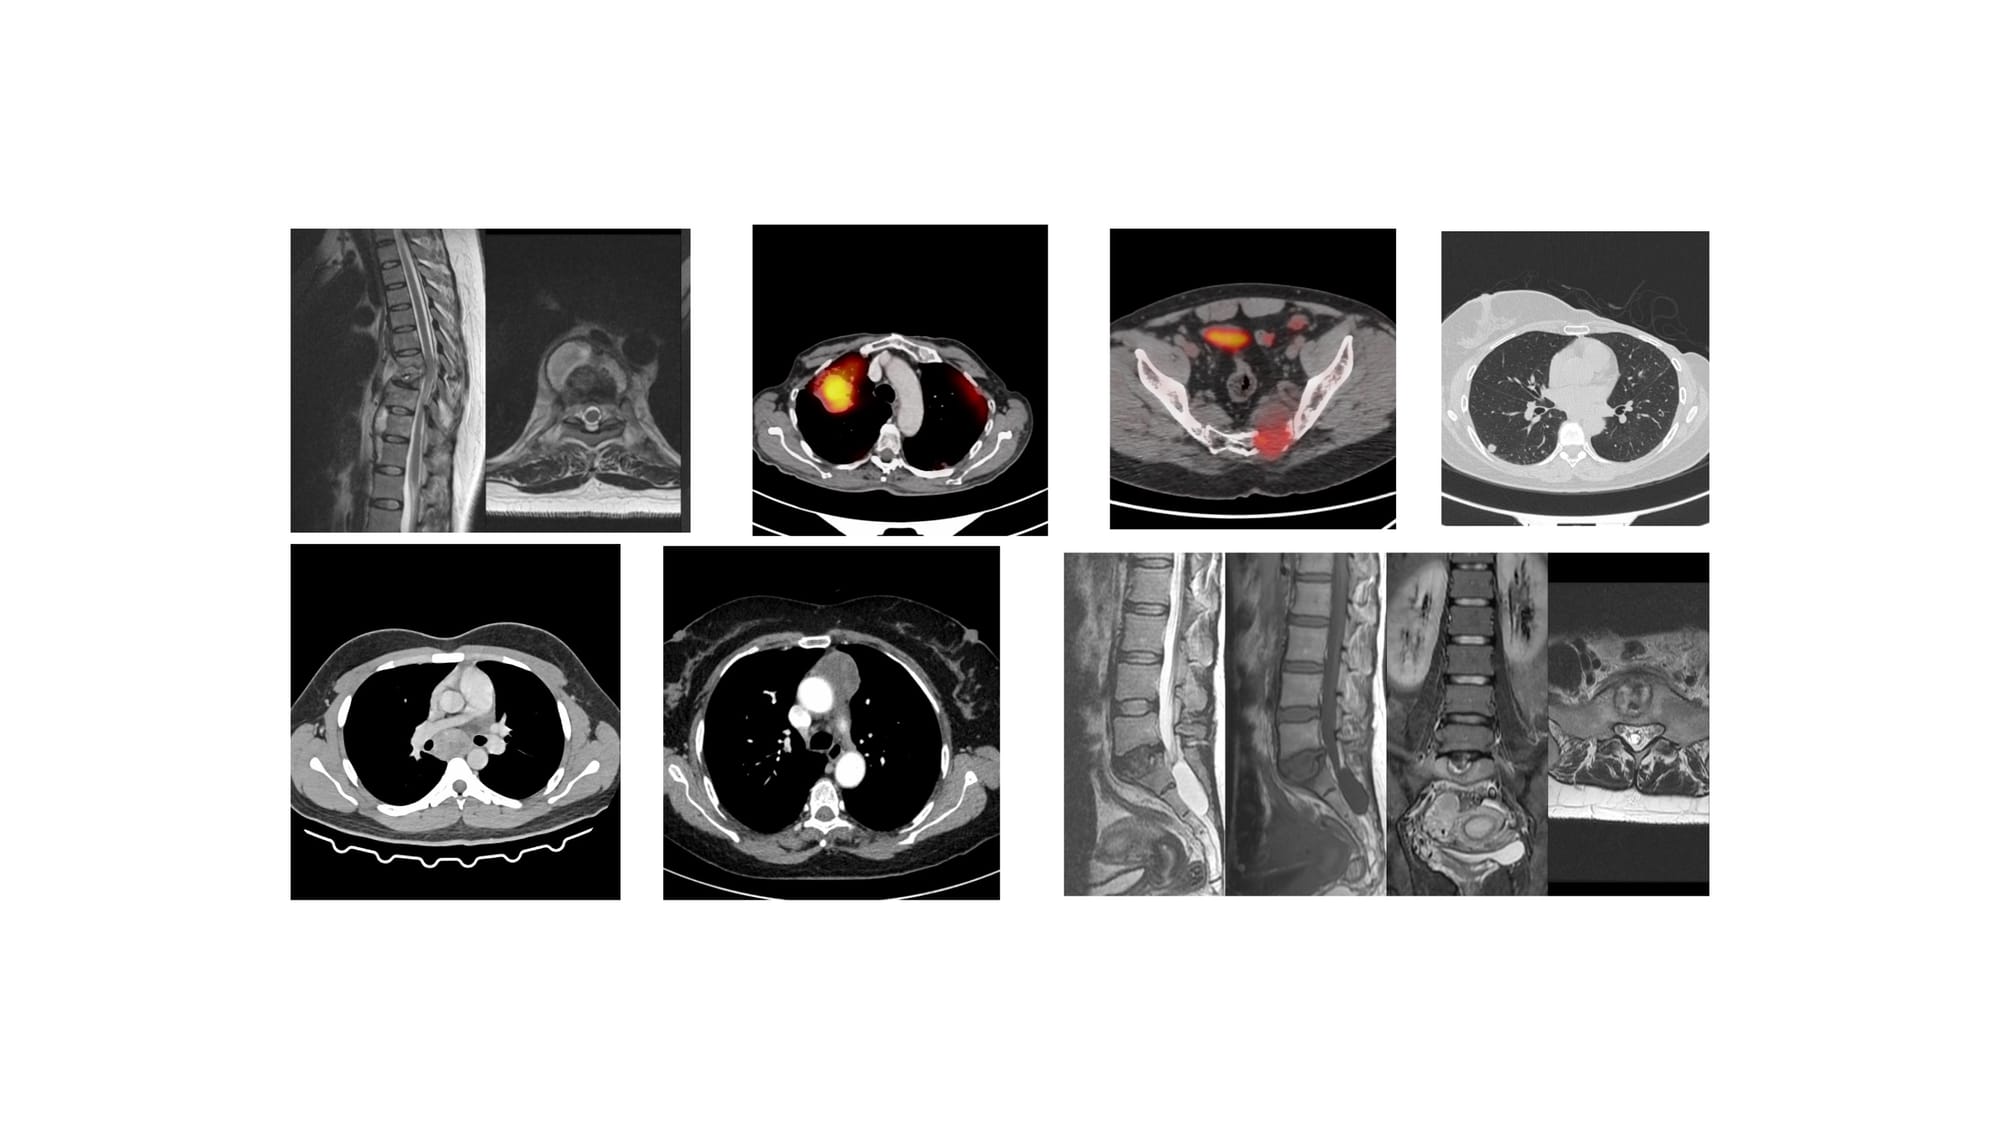

The 6 Cases for YouTube Live on 26 Feb at 7 PM Indian Standard Time

The 7 Cases for YouTube Live on 08 Jan at 7 PM Indian Standard Time